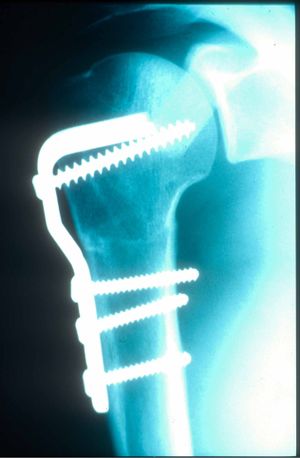

Osteotomy of the Lesser Tuberosity With the Attached Subscapularis (Hughes and Neer method)

Several authors modified McLaughlin’s method and described osteotomizing the lesser tuberosity with the attached subscapularis tendon and fixing it to the defective area.[36][30] The modified McLaughlin method provides additional bony support for the defective area and is preferred for patients when the injury is older than three weeks.[39] Depending on the importance of the bone loss, simultaneous iliac crest autograft, dry morselized allograft, fresh-frozen femoral head bone allograft can be perform.[40][41]

The surgery is performed in a beach chair position. The deltopectoral approach is used. First, the biceps tendon is identified as a landmark for the bicipital groove. The lower edge of the subscapularis tendon is detected in order to mark lesser tuberosity. Osteotomy of the lesser tuberosity is performed from lateral to medial, starting from the bicipital groove to the defect of the humeral head.[39] The lesser tuberosity with the attached subscapularis tendon is elevated in order to demonstrate the head and the glenoid. Reduction is performed and when achieved, the lesser tuberosity with the attached subscapularis tendon is fixed into the humeral head defect using ether screws, anchors or sutures.[42][41] Reported results are usually excellent.[43][41]